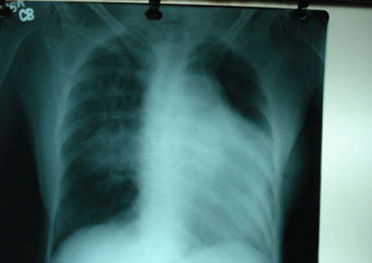

Pulmonary artery aneurysm is a very rare condition. Clinical experience is limited and current knowledge is mainly derived from autopsy findings, however, Pulmonary arterial aneurysms are being detected more frequently with modern techniques of echocardiography and angiography. We report a case of pulmonary artery aneurysm presenting with pulmonary hypertension. We will present a review of literature and discuss the differential diagnosis, presentation and management.